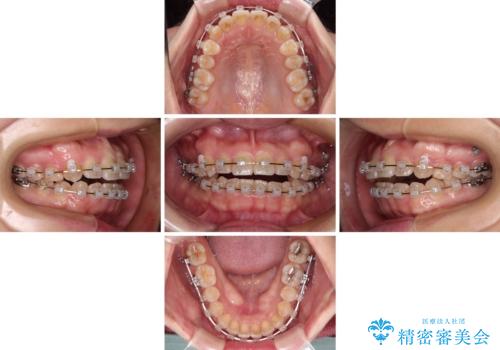

- クリアブラケット

- 1年7ヶ月

舌の突出癖により上下前歯が開咬となりましたが、舌のトレーニングと顎間ゴムの使用により、元々の被蓋関係に改善することができました。

アンカースクリューを用いて、出っ歯仕上がりを回避し、正中位置も改善することができました。